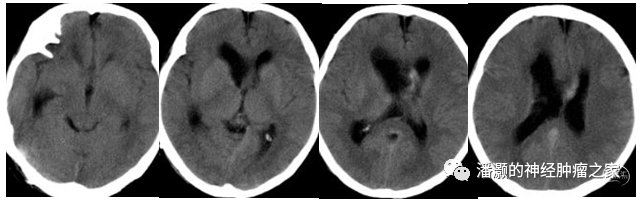

术后6天复查头颅CT观察脑室情况,基本同术前,无明显脑积水出现。